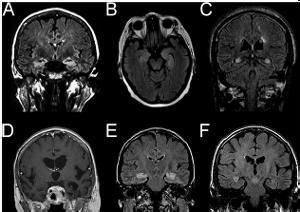

2.MRI:在中顳葉、海馬扣帶回島葉以及杏仁核等結構可見到異常的信號影像。